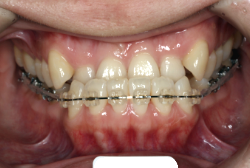

「ものがうまく噛めない」という主訴で来院したケースです。診断の結果、「骨格性反対咬合に伴う咬合不良+軽度叢生」と判明しました。原因としては特に下顎の左側が過成長したため、骨格性反対咬合になり、特に左側での噛み合わせが非常に悪くなっていると診断しました。初診時の写真を見ると、上下の正中線の大きなズレ、左側の噛み合わせの不良がはっきり分かります(黄色の矢印と緑の矢印は一致しているのが正しい状態です)。

治療中の写真で、アンカースクリューより歯を後ろへ牽引しているのがお分かりいただけるかと思います。牽引を1年ほど続け、途中補助的に上下にゴムをかける(これを顎間ゴムと言います)手法なども追加し、全体で21ヶ月で治療を終えることが出来ました。